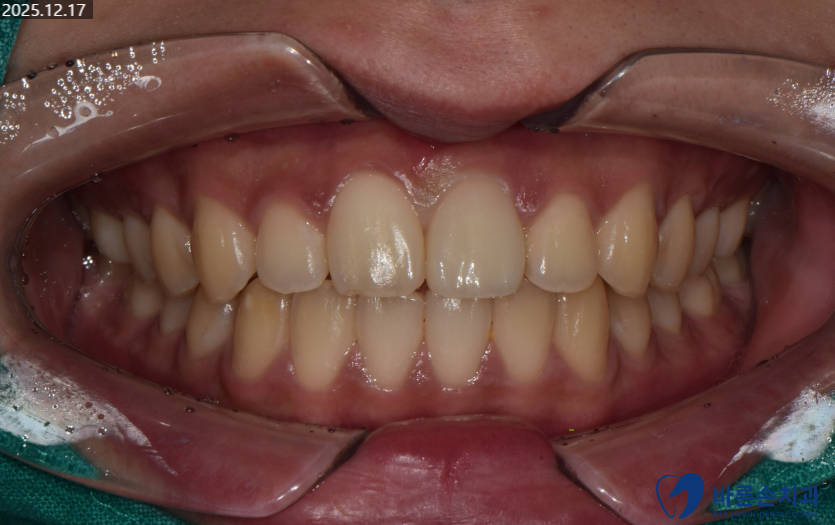

완성된 보철물이 나와 세팅을 합니다.

다행히 원래 치아와 비슷하게

감쪽같이 치료가 잘 마무리 되었습니다.